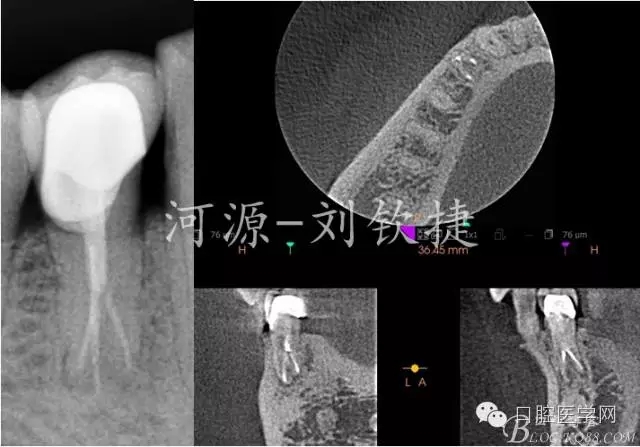

輔助檢查:X-Ray顯示44未做根管治療,根管影像在根中1/2突然消失,且明顯可見近遠(yuǎn)根,根尖區(qū)有模糊陰影;拆除冠修復(fù)體后CBCT顯示44C型根管,頰側(cè)1根,舌側(cè)2根,頰側(cè)頸1/3白色影像達(dá)髓腔??膳袛嘧畛蹙歪t(yī)的原因是楔缺導(dǎo)致的牙髓炎。

由于條件不足下,在X-Ray監(jiān)測下完成根充↑

2)下頜第一前磨牙的根管大部分為單根管,雙根管的發(fā)生率約為25%,三根管的發(fā)生率不足1%,根管治療術(shù)前拍攝X線片是為了檢查根管系統(tǒng)是否存在細(xì)小根管、根管鈣化、彎曲根管、變異根管,為根管預(yù)備做準(zhǔn)備。對于多根管發(fā)生率較高的牙齒應(yīng)常規(guī)術(shù)前加拍偏投射位X線片提高發(fā)現(xiàn)率,也可常規(guī)進(jìn)行CBCT檢查來彌補(bǔ)X線片的不足,進(jìn)一步三維的了解根管系統(tǒng),做到最大限度的術(shù)前評估與治療方案的制定;